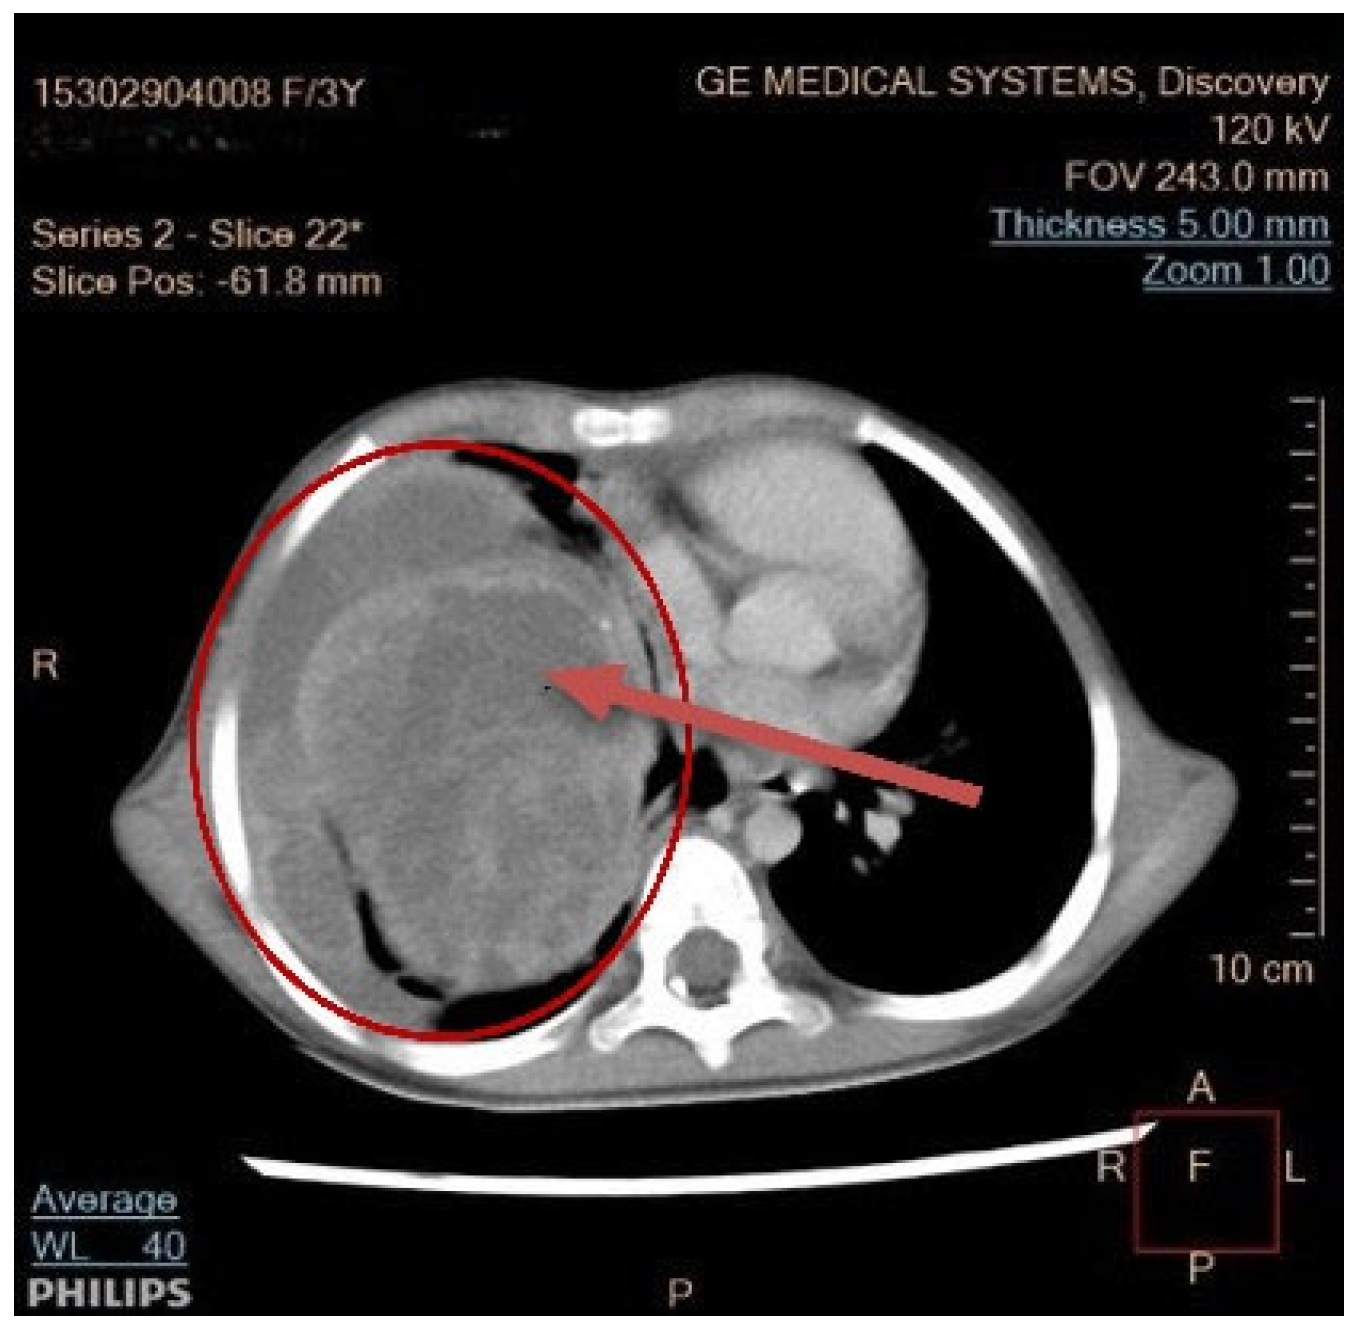

3.2. Diagnosis

3.4. Tumor Localization and Size